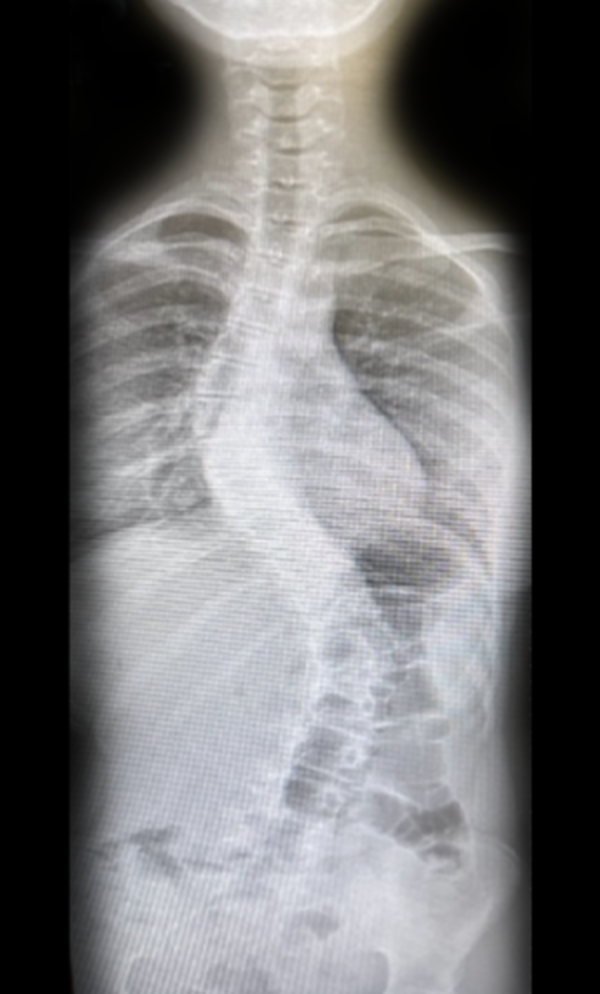

Gallery : Before - After

• Scoliosis surgery with small incisions using flexible correction technology (VBT) and growth-preserving techniques such as remotely controlled magnetic growing rods

• Scoliosis for children and adults